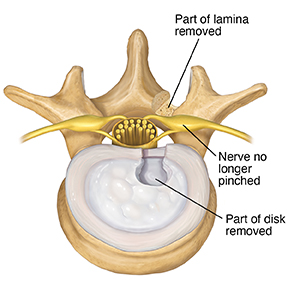

Removing disk

During a microdiskectomy, some disk is removed. In most cases, a laminotomy must first be done to expose the damaged disk. The part of the disk outer wall and soft center that presses on the nerve can then be taken out. Any disk matter that is loose or that may cause problems in the future is also taken out. There is often enough disk still there to cushion the vertebrae.

|

| A part of the disk is removed to take pressure off the nerve. |